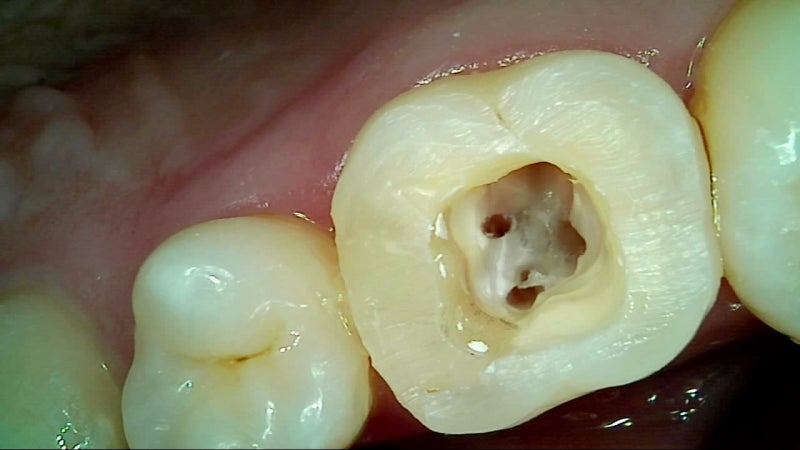

- 신경 접근: 충전물 제거 후 내부 접근

- 감염 제거 및 소독: 근관 확대·세척

- 임시 충전: 약제 삽입 및 임시 밀봉